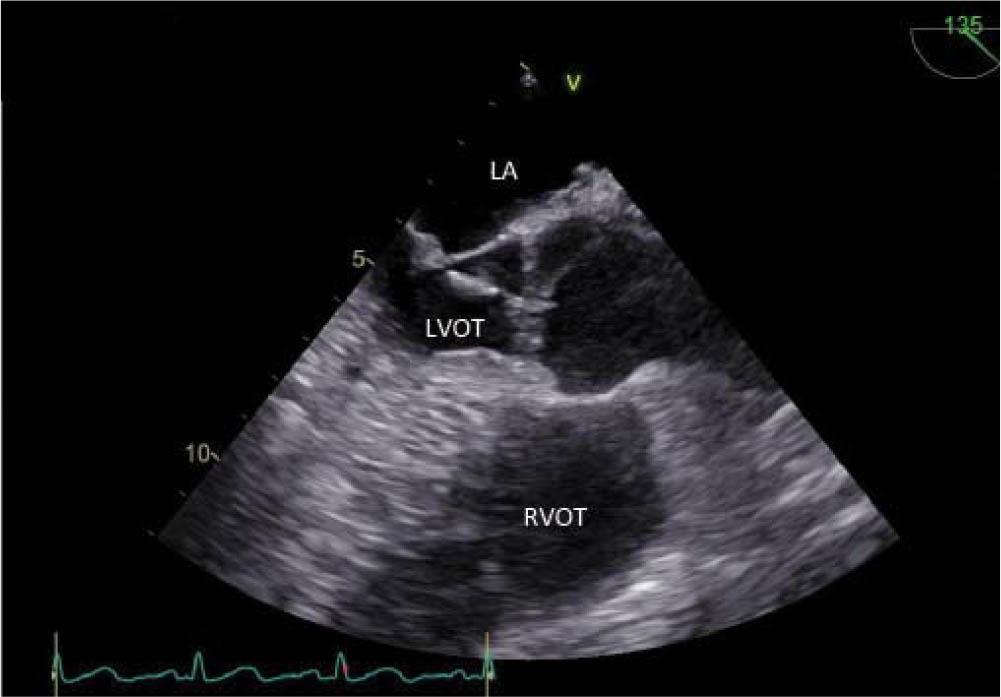

Transthoracic echocardiography (TTE) at admission and afterwards transesophageal echocardiography (TEE), both performed with GE Vivid E9, revealed a hyperechogenic mass, with independent movement, attached to the posterior mitral leaflet, on the atrial surface, with a diameter of 6/6 mm, prolapsing A2 scallop and mild mitral regurgitation (Figure 2). At the same time, it revealed a large mobile mass (diameter 18/4 mm) on the aortic valve, attached to all three leaflets (Figure 3), prolapsing in the left ventricular outflow tract (LVOT) (Figure 4) with high probability of non-coronary cusp (NCC) perforation without hemodynamic impact (Figure 5). Left ventricular size and ejection fraction were normal (Figure 6).

Figure 4

Transesophageal echocardiography aortic valve long-axis-view 18 mm long, mobile, hyperechogenic mass attached to the ventricular side of the aortic valve. The echocardiographic appearance is suggestive for vegetation.